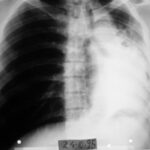

2003: 61 yaşındaki erkek hasta prostat adenokarsinomu ve yaygın kemik metastazı tanısı aldı.

Tuşe rektalde prostat büyümüş ve sertti.

2004 Mart (3. Ay)

Ağrıları kayboldu, metastaz bulgularında belirgin düzelme görüldü.

2004 Haziran (6. Ay)

Başındaki tümör tamamen geçmişti.

Yapılan sintigrafi patolojik bulgu göstermedi.

2005 Ocak: Sintigrafi tamamen normal

2006: Hasta normal yaşantısını sürdürüyordu